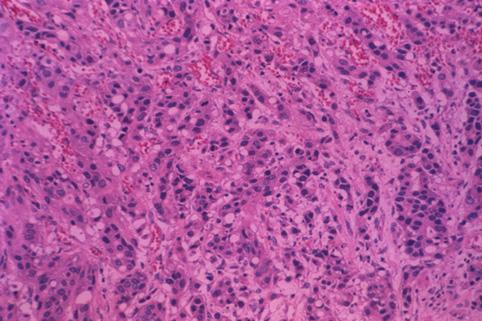

疾患(病理主体)の分類悪性上皮性腫瘍/腺癌

部位(臓器別)胃(部位)/2つ以上

検査方法ミクロ

腫瘍の肉眼分類3型(潰瘍浸潤型)/

病変の最大径(ミリ)40以上

腫瘍の深達度mp